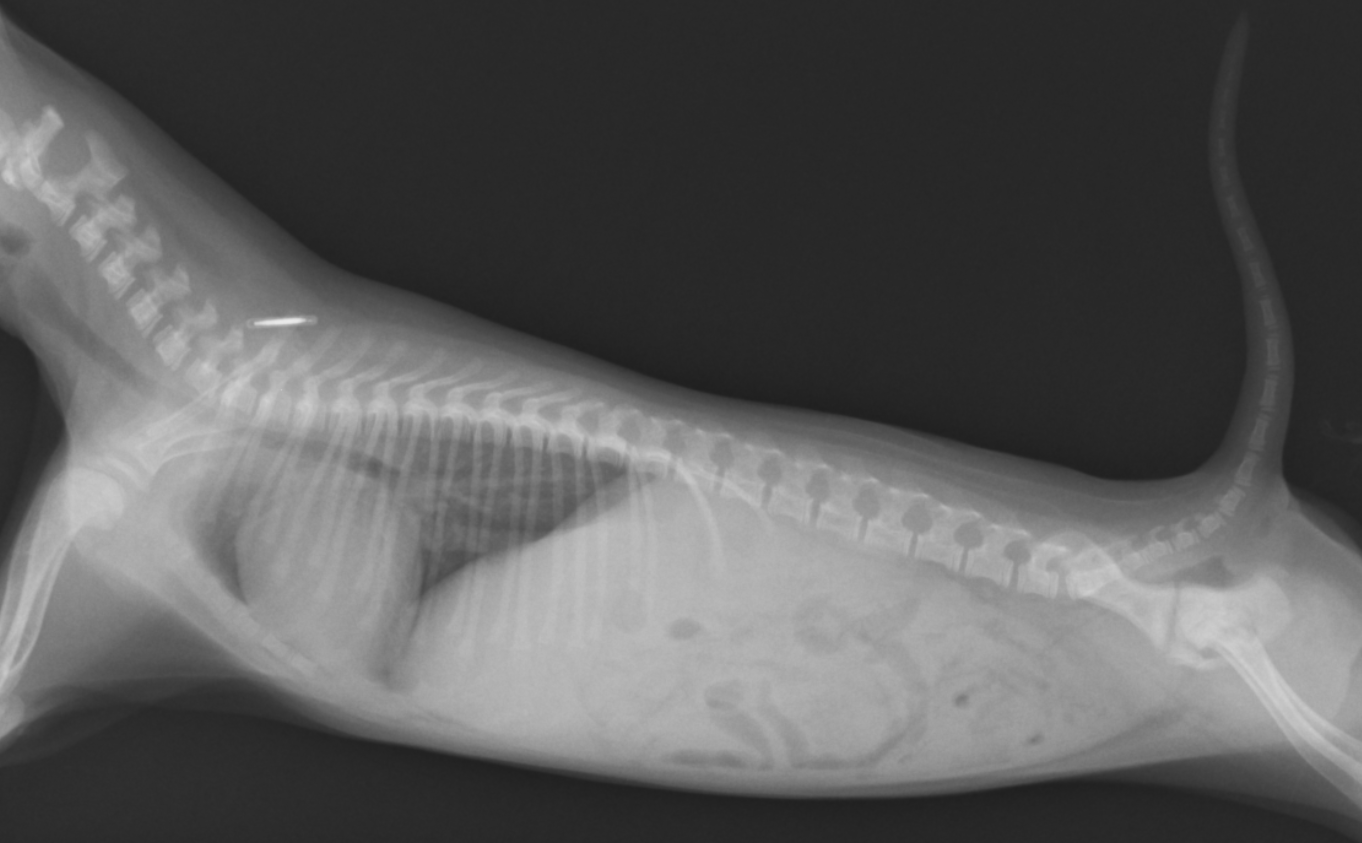

今回ご紹介するのは1週間前に軟便から始まり持続的な下痢を主訴に来院された症例をご紹介します。症例は、2ヶ月齢のポメラニアン、未避妊雌で来院前日から食欲が落ち元気がないということでした。当院ではまず血液検査、X線検査、糞便検査を行いました。

X線検査では、特に大きな異常はありませんでした。